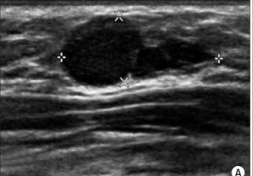

Fat Necrosis

Fat necrosis is caused by damage to fat cells, typically from direct trauma (e.g. seatbelt injury, biopsy, breast surgery such as implant removal or reconstruction). Radiation therapy and anti-coagulants may also cause fat necrosis to develop. Fat necrosis may be felt as a lump, otherwise it is detected via mammogram or ultrasound. They can resemble breast cancer on mammogram, so a biopsy may be needed to exclude malignancy. Usually fat necrosis will resolve on its own without treatment.